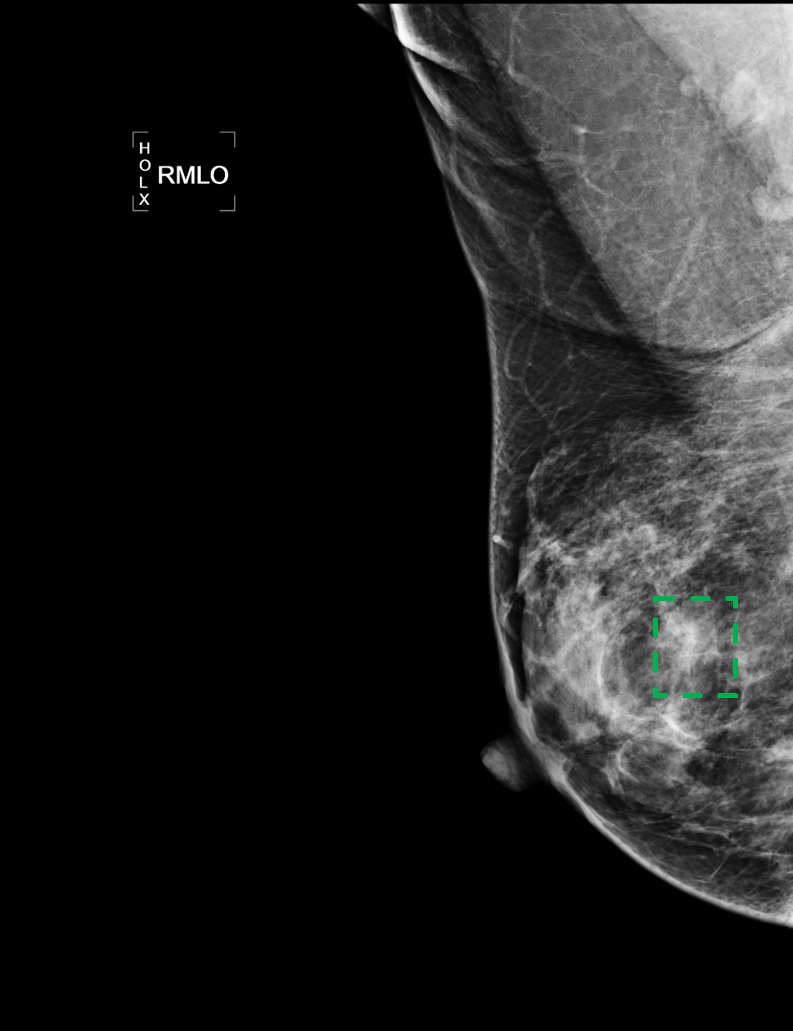

Deep learning object detection algorithm has been widely used in the task of classifying or detecting objects of natural images [3] and [8], and are receiving more and more attentions on its usage in medical image analysis. However, current object detection tasks are all based on the data annotated with object classes and their bounding boxes, those images which are not considered during labeling may contain regions or objects that are similar to the target ones, and may be misclassified in the testing stage. This phenomenon is critical in medical image analysis. For example, as shown in Fig.(1), a healthy mammography may contain benign or normal regions whose features are very similar to a malignant lesion. On the other hand, when doctors perform labeling, they usually search for medical records of patients that are diagnosed as cancer first, and only selected samples are labeled and used for training. As a result, those healthy samples that contain suspected malignant regions are likely to be classified as malignant.

In the following, we define a mammography with malignant lesions as a positive image, and those malignant lesions as positive targets or targets. All the other mammography are defined as negative images, including those images contain benign or normal regions that are highly suspect to be malignant(as shown in Fig.(1)). And without loss of generality, we called those highly suspected malignant regions as suspected target regions. Within the datasets we used, all the positive targets are annotated with bounding boxes to indicate their precise locations and all the negative images do not have any annotation.